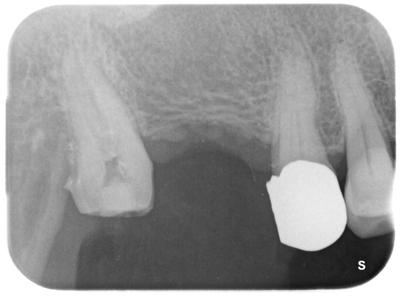

術前

年配の方で、歯髄腔はハッキリしない。

前医は途中まで進めたようだが。